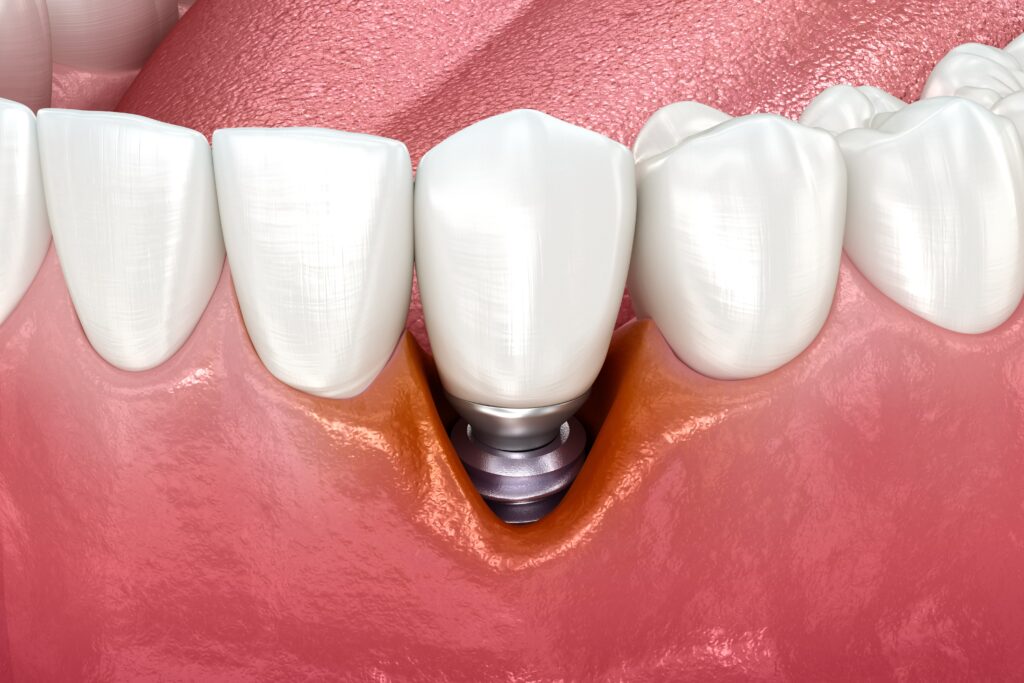

시간이 지나 임플란트 주위에 염증이 생기거나 뼈와의 결합이 약해질 경우, 임플란트가 흔들리거나 통증이 동반될 수 있습니다.

이때는 단순히 보철물을 교체하는 것으로는 해결이 어렵기 때문에, 임플란트 재식립을 고려해야 하는 부분입니다. 재식립은 기존 임플란트를 제거한 뒤 손상된 잇몸뼈를 회복시키고, 새로운 인공치근을 다시 식립하는 과정을 말합니다. 잇몸뼈 상태와 염증 정도에 따라 즉시 식립이 가능한 경우도 있고, 뼈 이식 후 일정한 치유 기간을 거쳐 다시 임플란트를 심기도 합니다.

임플란트 재식립은 기존에 심어둔 인공치근이 기능을 상실했을 때 이를 제거하고, 다시 새로운 임플란트를 식립하는 과정을 말합니다.

기존 임플란트 주위에 염증이 생기거나 뼈와의 결합이 약해져 흔들릴 경우, 그 상태로 방치하면 주변 조직 손상이나 잇몸뼈 흡수가 더 진행될 수 있습니다. 따라서 손상 부위를 정리하고 뼈 상태를 회복한 뒤, 새로운 임플란트를 심어 기능과 심미성을 되살리는 것이 재식립의 핵심입니다.